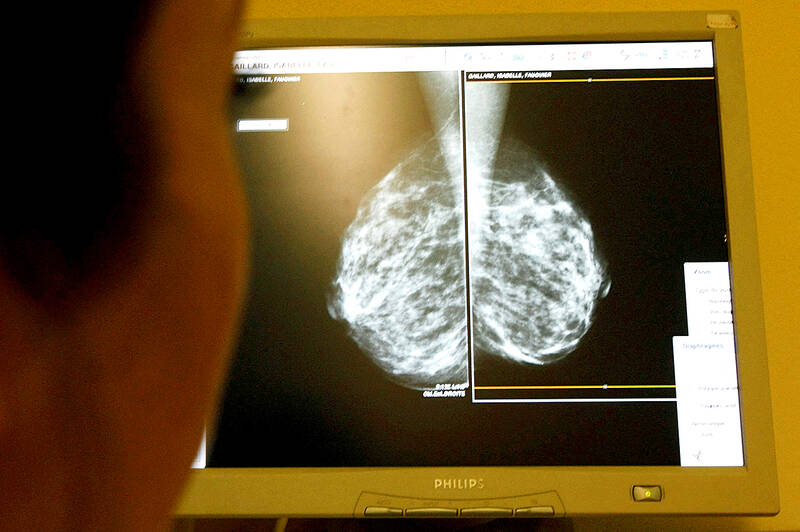

Photo: Reuters

The use of artificial intelligence in breast cancer screening is safe and can almost halve the workload of radiologists, according to the world’s most comprehensive trial of its kind.

Screening can improve prognosis and reduce mortality by spotting breast cancer at an earlier, more treatable stage. Preliminary results from a large study suggest AI screening is as good as two radiologists working together, does not increase false positives and almost halves the workload.

The interim safety analysis results of the first randomized controlled trial of its kind involving more than 80,000 women were published in the Lancet Oncology journal.

In total, 244 women (28 percent) recalled from AI-supported screening were found to have cancer compared with 203 women (25 percent) recalled from standard screening. This resulted in 41 more cancers being detected with the support of AI, of which 19 were invasive and 22 were in situ cancers.

The use of AI did not generate more false positives, where a scan is incorrectly diagnosed as abnormal. The false-positive rate was 1.5 percent in both groups.

There were 36,886 fewer screen readings by radiologists in the AI group compared with the group receiving standard care, resulting in a 44 percent reduction in the screen-reading workload of radiologists, the authors said.

But the interim analysis concludes: “AI-supported mammography screening resulted in a similar cancer detection rate compared with standard double reading, with a substantially lower screen-reading workload, indicating that the use of AI in mammography screening is safe.”